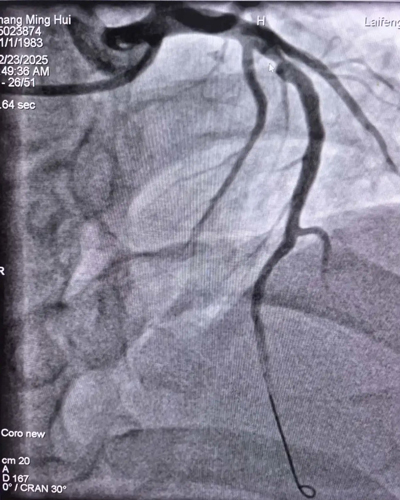

手术前血管情况 手术后血管情况